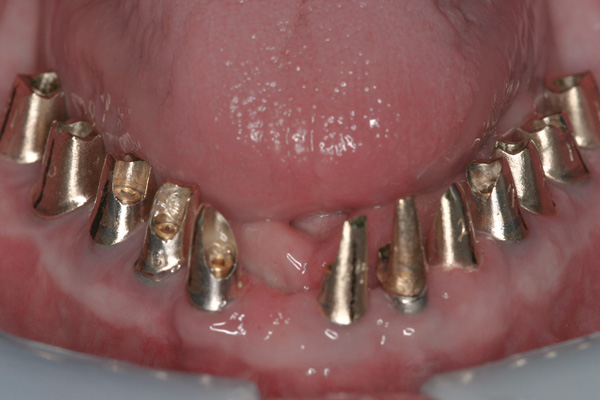

Background: This patient had a failing maxillary dentition and refused to wear a removable prosthesis. A staged approach was employed to retain some of his natural tooth abutments, and recession was noticed at the time of the impression for the second group of implants. Figure 1 shows the patient following insertion of the first set of implant custom abutments; the adjacent natural teeth are still present to support the provisional bridge. Seven months later, as shown in Figure 2, those first-stage custom abutments exhibited evidence of 1 mm to 3 mm of recession.

Results: A decision was made to re-prepare all of the abutments intraorally (Figure 3) so that all abutment margins would be at or below the gingival margin. (Of note, teeth Nos. 8 and 9, also shown in Figure 3, were later submerged for the case to be fully implant-supported.) While re-preparation greatly improved the esthetics of the final result, it required retraction cord placement, new impressions, and new castings.

(Note: A separate but similar type of case shown in Figure 4 and Figure 5 further illustrates intraoral abutment re-preparation.)

Figure 3 Abutments re-prepared intraorally.

Figure 3

Figure 4 Following osseointegration of an implant at No. 12, recession was observed at the fixture-level impression stage of No. 13; it was decided to re-prepare the margins of the CAD/CAM custom abutment of implant No. 12. Retraction cord was placed prior to preparation to avoid tissue injury and improve visibility of both tooth No. 11 and the implant custom abutment margin. As expected, recession was greater along the distal side of abutment No. 12, adjacent to the healed extraction/newer implant site.

Figure 4